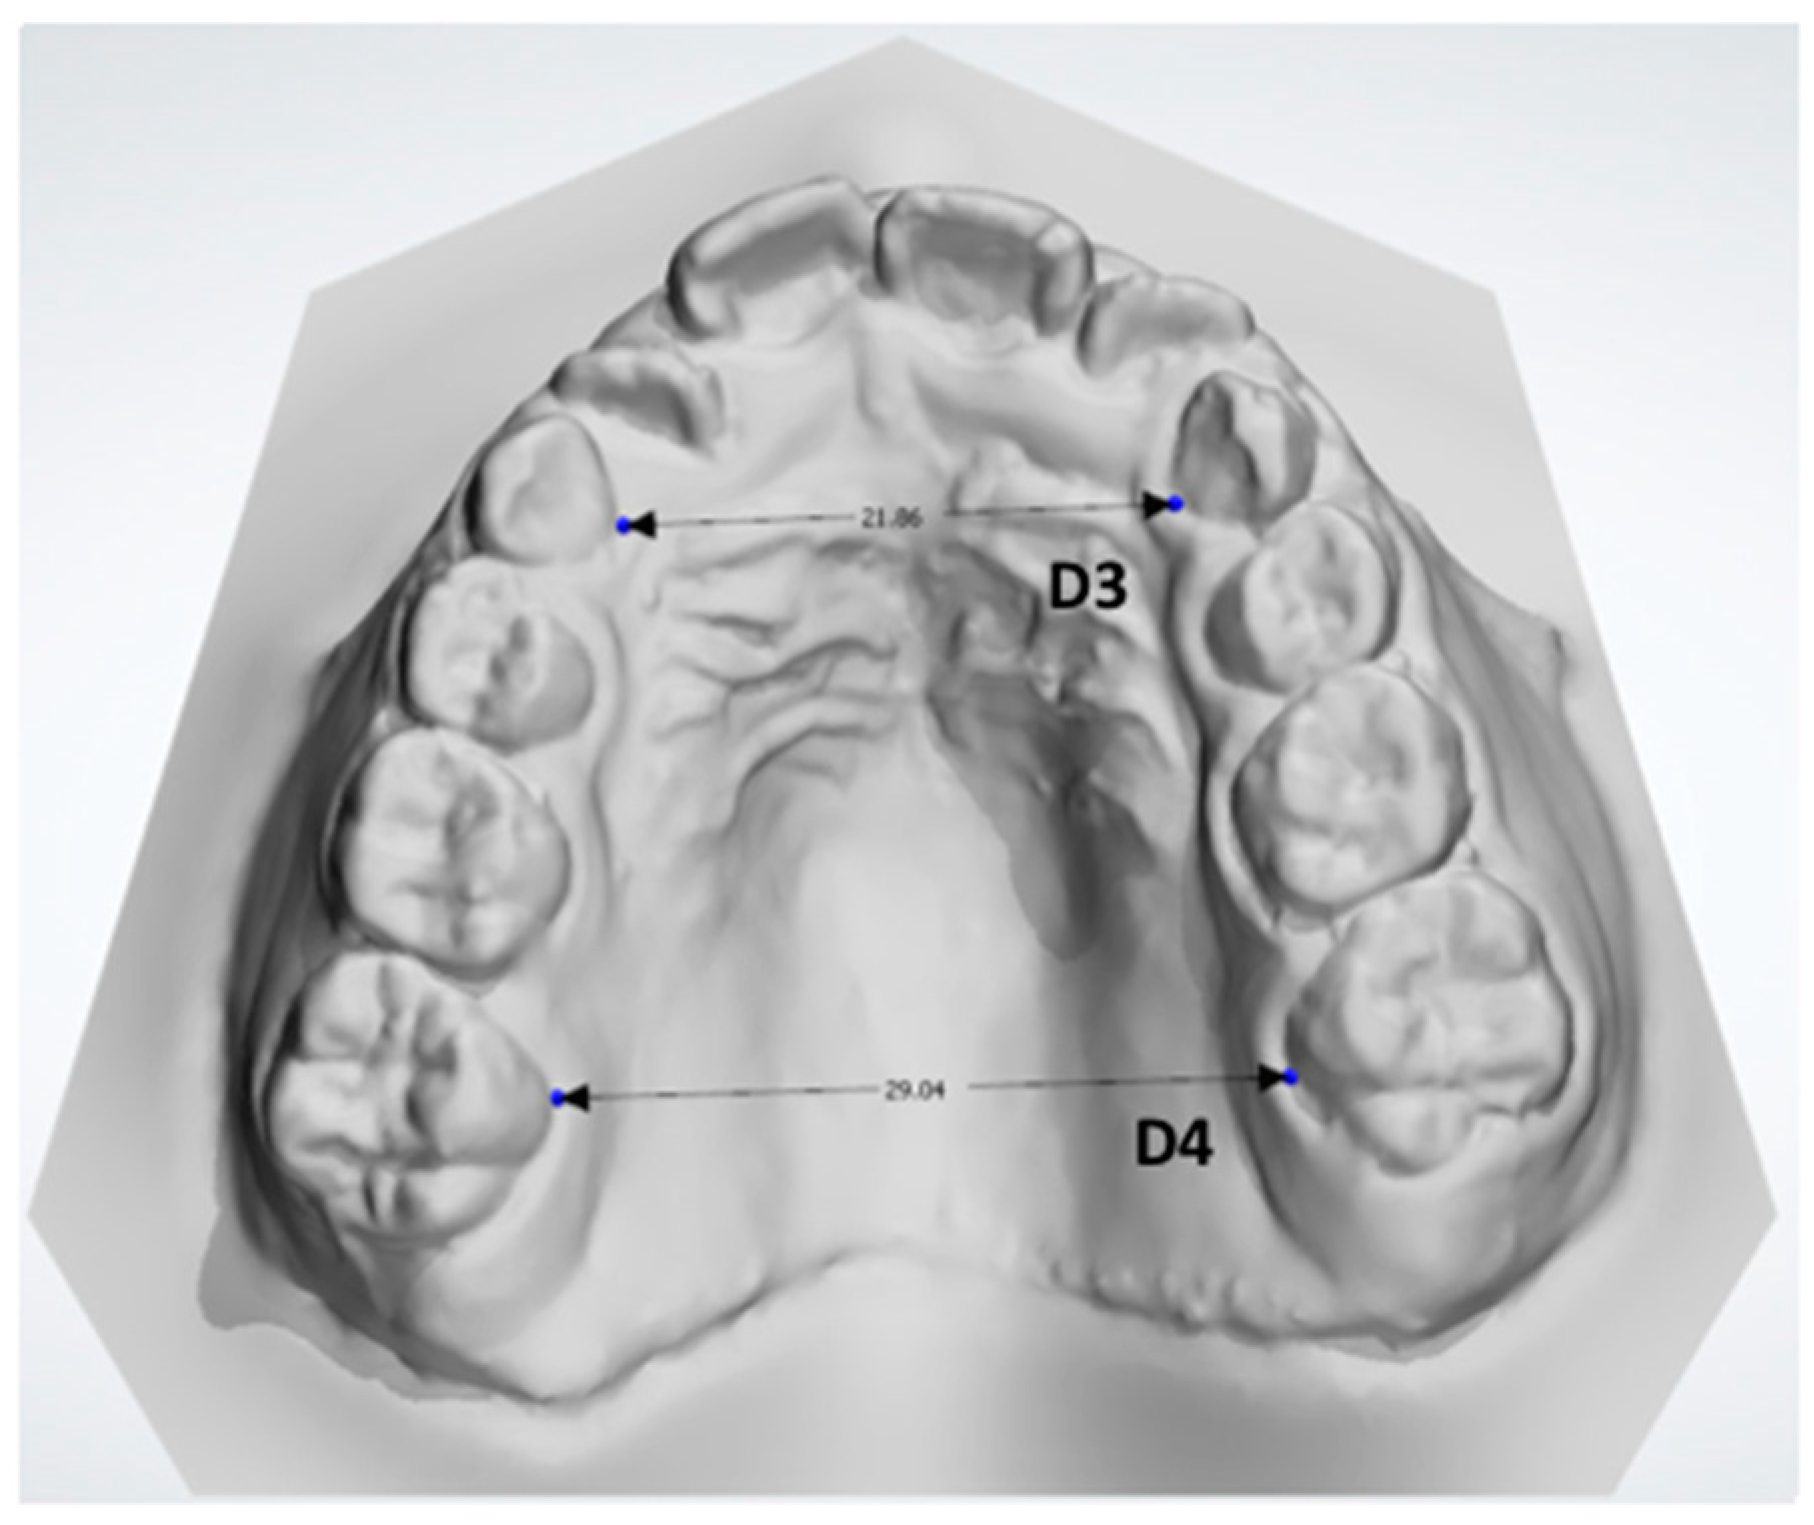

- D3: the distance between the midpoint at the dento-gingival junction of the two primary canines (Figure 7).

Figure 7. Total linear transversal measurements: distance between the midpoint at the dento-gingival junction of the two primary canines (D3) and the distance between the midpoint at the dento-gingival junction of the two first molars (D4). - D4: the distance between the midpoint at the dento-gingival junction of the two first molars (Figure 7).

These measurements provide information about the transversal diameter of the maxillary arch (D3-D4) and about the emi-transversal diameters to identify potential linear asymmetry between both sides (D1–D2).

Transversal measurements of the maxilla showed a distance of 21.86 mm between primary canines and 29.04 mm between primary second molars. According to the study of McNamara and coauthors [4,24], a clinical value of inter-molar distances ≤ 31 mm should be considered as a cut-off parameter for diagnosis of narrowed maxillary requiring treatment by maxillary expansion. However, considering that the patient was only 6 years old and that she presented full primary dentition, this cut-off could be higher considering the potential growth of the patient [24]. Thus, the maxillary contraction could be considered as moderate in severity.

Emi-lateral distances to the MPP at the primary canines level were 12.24 mm at the right side and 11.60 mm at the left side. The same distances at the first molars level were 16.80 mm at the right side and 16.82 mm at the left side. Thus, no relevant differences were detected between right and left side concerning transversal linear measurements. Additionally, the deviation analysis of mirrored superimposed models of the maxilla revealed a good coincidence between the two models, as shown by the the colored map (green color). In particular, Figure 9 shows no areas of mismatching (intense blue and intense red contours) between the original and specular model either in the palatal vault or along the profile of the dento-alveolar processes.